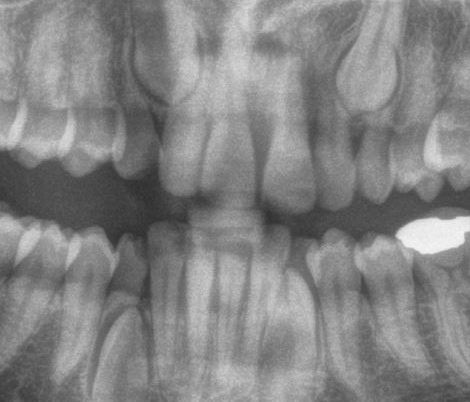

Impacted Canine

Impacted Canines, Same Patient as above